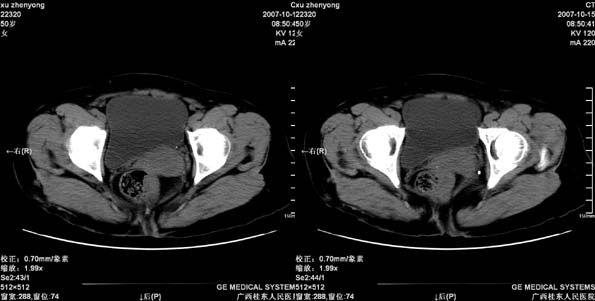

患者,女 50岁.会阴部坠胀感一月余,有痔疮病史,近期有便血;患者今年5月分结肠镜检查未见异常(由于患者不愿意ct增强扫描)没做增强,现准备手术,请各位老师会诊.

直肠下端及肛门周围可见软组织改变,如果5月份检查的结肠镜结果可靠,那么本病例痔的可能性还是很大的。肿瘤生长的不会如此之快。

直肠壁增厚明显,周围脂肪间隙模糊,前方与阴道后壁分解不清。考虑直肠癌可能性大!

这个患者做了手术,术中直肠及会阴部均求见肿瘤,探查要中未作特殊处理.患者准备复查,我会急时上传图象